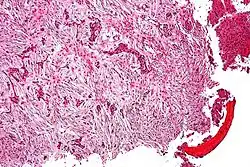

Micrograph (using H&E stain) of an adamantinoma showing the biphasic histomorphology. | |

Adamantinoma (from Greek adamantinos 'very hard'[1]) is a rare bone cancer, making up less than 1% of all bone cancers.[2] It almost always occurs in the bones of the lower leg[3] and involves both epithelial and osteofibrous tissue.[4]

Histologically, islands of epithelial cells are found in a fibrous stroma. The tumor is typically well-demarcated, osteolytic and eccentric, with cystic zones resembling soap bubbles.[2]